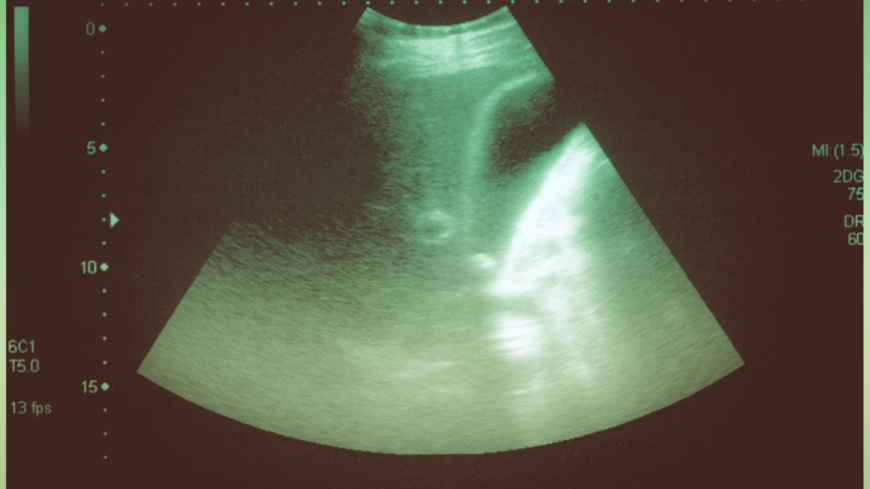

En undersökning med ultralljud brukar göras för att bekräfta diagnosen. Några andra undersökningar som ibland görs är datortomografi, magnetresonansundersökning och ECRP. Under en ECRP-undersökning kan man i vissa fall också ta bort gallstenar under undersökningens gång.